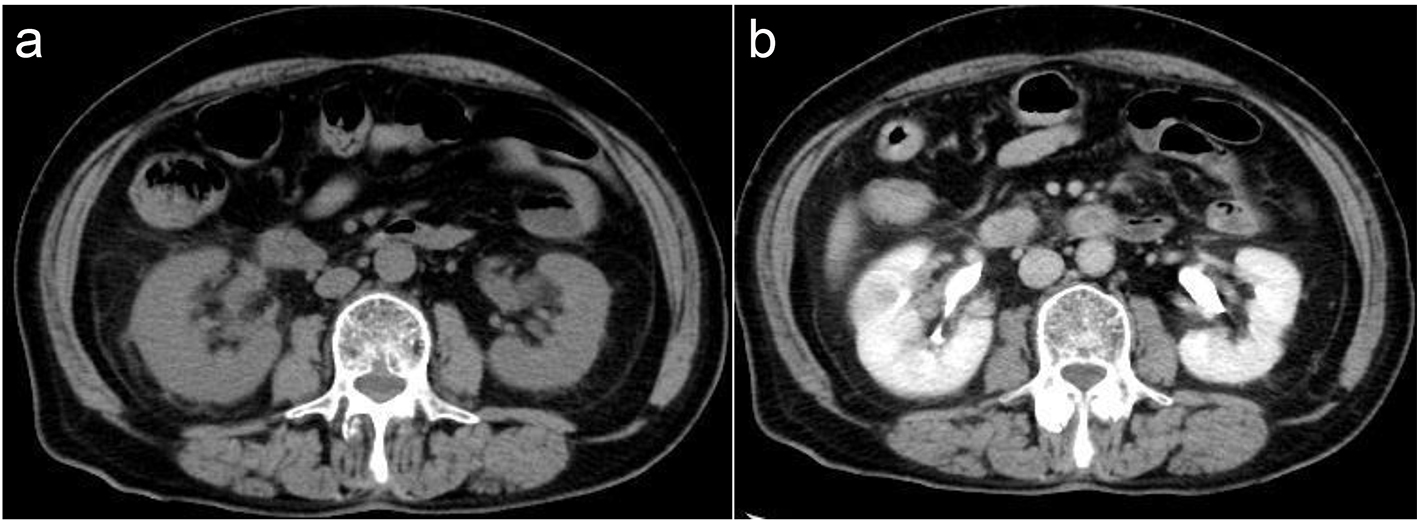

A 78-year-old female presented to our hospital with complaints of fatigue, headache, and low grade fever lasting for a couple of days. Her medical history included hypertension, which was treated using medicine. She had no history of urinary tract infection. Upon arrival, her blood pressure was 133/78 mm Hg, heart rate was 76 beats/min with regular rhythm, blood oxygen saturation was 99% under atmospheric conditions, and body temperature was 37.2 °C. Blood chemistry analyses revealed severe inflammation (18,500 WBCs/μL with 79.8% neutrophils and 22.0 mg/dL C-reactive protein), coagulant dysfunction (72% prothrombin, 45.5 s activated partial thromboplastic time, 1,014 mg/dL fibrinogen, and 1.5 μg/mL D-dimer), and unimpaired glucose tolerance (110 mg/dL glucose and 5.9% hemoglobin A1c). Further, mildly decreased albumin (3.3 g/dL), mildly increased total bilirubin (1.5 mg/dL), 160 IU/L γ-glutamyltransferase, 702 IU/L alkaline phosphatase, and 354 IU/L lactate dehydrogenase were also revealed. Chest radiography revealed no shadows indicative of pneumonia. Urinalysis revealed 1 - 4 WBCs/HPF and 5 - 9 RBCs/HPF with no bacteria. Urinary and blood culture were negative for bacteria. Although she had no abdominal symptoms, non-contrast, whole-body CT was performed to further explore the possibility of infection. Non-contrast CT revealed signs of fat stranding in the pararenal space and mild swelling of the right kidney suggestive of infection (Fig. 3a). Contrast CT revealed wedge-shaped defects as well as enhancement in the right kidney which suggests that infection has been present for some time (Fig. 3b). She was then diagnosed with AFBN and antibacterial treatment was initiated (Fig. 4). After 3 weeks of antibacterial treatment, chemical analyses and her symptoms improved.

![]() Click for large image | Figure 3. (a) Signs of fat stranding in the pararenal space and mild swelling of the right kidney suggestive of infection. (b) Wedge-shaped detects in the right kidney consistent with AFBN. |